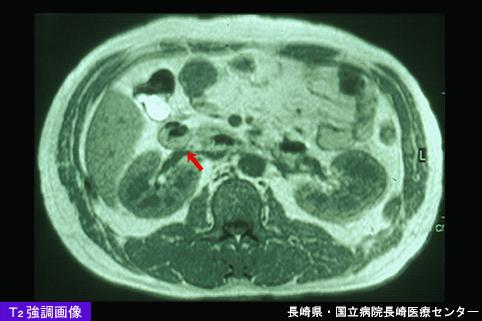

恶性非上皮性肿瘤 平滑肌肉瘤(小肠)

利用CT可以推断肿瘤部位的,利用小肠造影做出诊断的空肠胃肠间质瘤

疾病(病理主体)的分类

恶性非上皮性肿瘤/平滑肌肉瘤

部位(按器官分)

小肠/空肠

检查方法

MRI

肿瘤最大直径

40以上

肿瘤的深度

mp